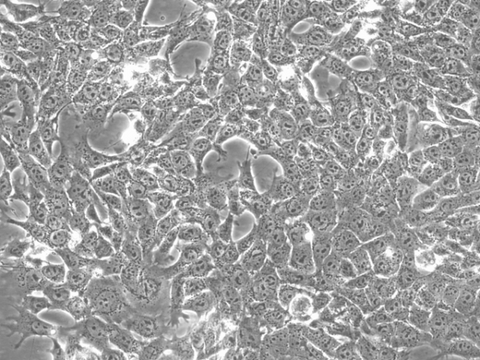

4T1 Cells

Description:

Stable reporter cell lines:

Our 4T1 reporter cell lines can be tracked in vivo, making them great tools for studying the mechanisms of tumor growth and metastasis, as well as evaluating the effects of various drugs or therapies in animals. Our 4T1 cells are available with a variety of different reporters, including the murine sodium iodide symporter (mNIS), firefly luciferase (Fluc), enhanced green fluorescent protein (eGFP), or near-infrared fluorescent protein (iRFP). Several dual reporter 4T1 cell lines are available to facilitate multi-modality imaging.